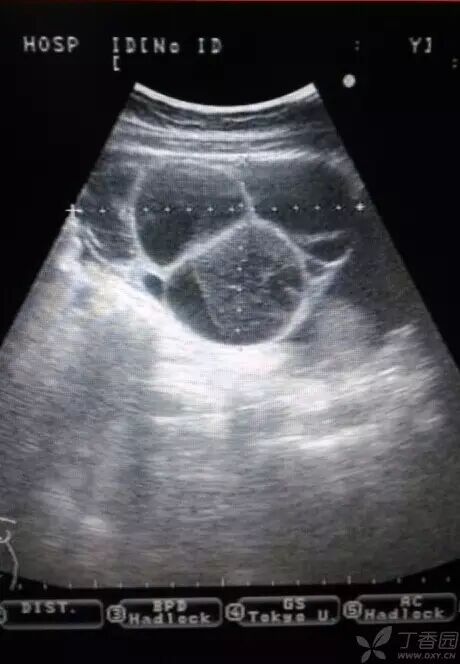

病例2(由丁香园注册用户「荷瓣111」提供):患者女,28岁,结婚5年未孕,应用促排卵药治疗2个月后,自觉腹部膨隆,呼吸困难。

超声所见如下图所示:

图1~3 显示子宫正常,盆腹腔可见两个相依的囊性肿物,其内见多条光带分隔,子宫被压在增大的卵巢下方

图4 显示肝肾区的腹腔积液